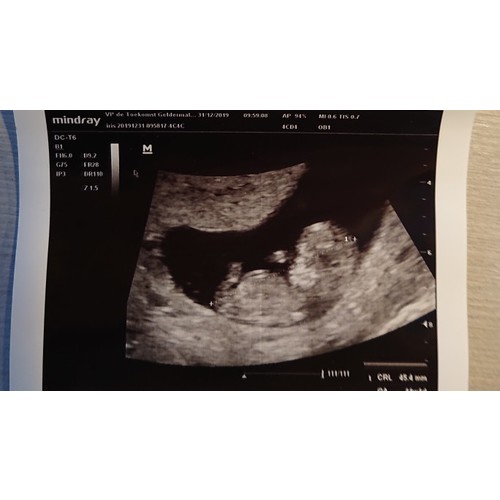

Deze vind ik lastig, als ik naar de onderste foto kijk neig ik naar boy, en bij de bovenste girl. Je hebt niet nog een foto in zn geheel dat we de nub erbij pakken?

Ik neig meer naar boy, goeie kaaklijn. Je bent nu 11 weken zie ik dat is het moment dat het geslacht meer 'vorm' krijgt dus ben benieuwd of het 'pimpeltje' inderdaad omhoog gaat staan bij je volgende echo:-)

Ik neig meer naar girl. Een hele mooie baby in ieder geval dat zie ik zo al